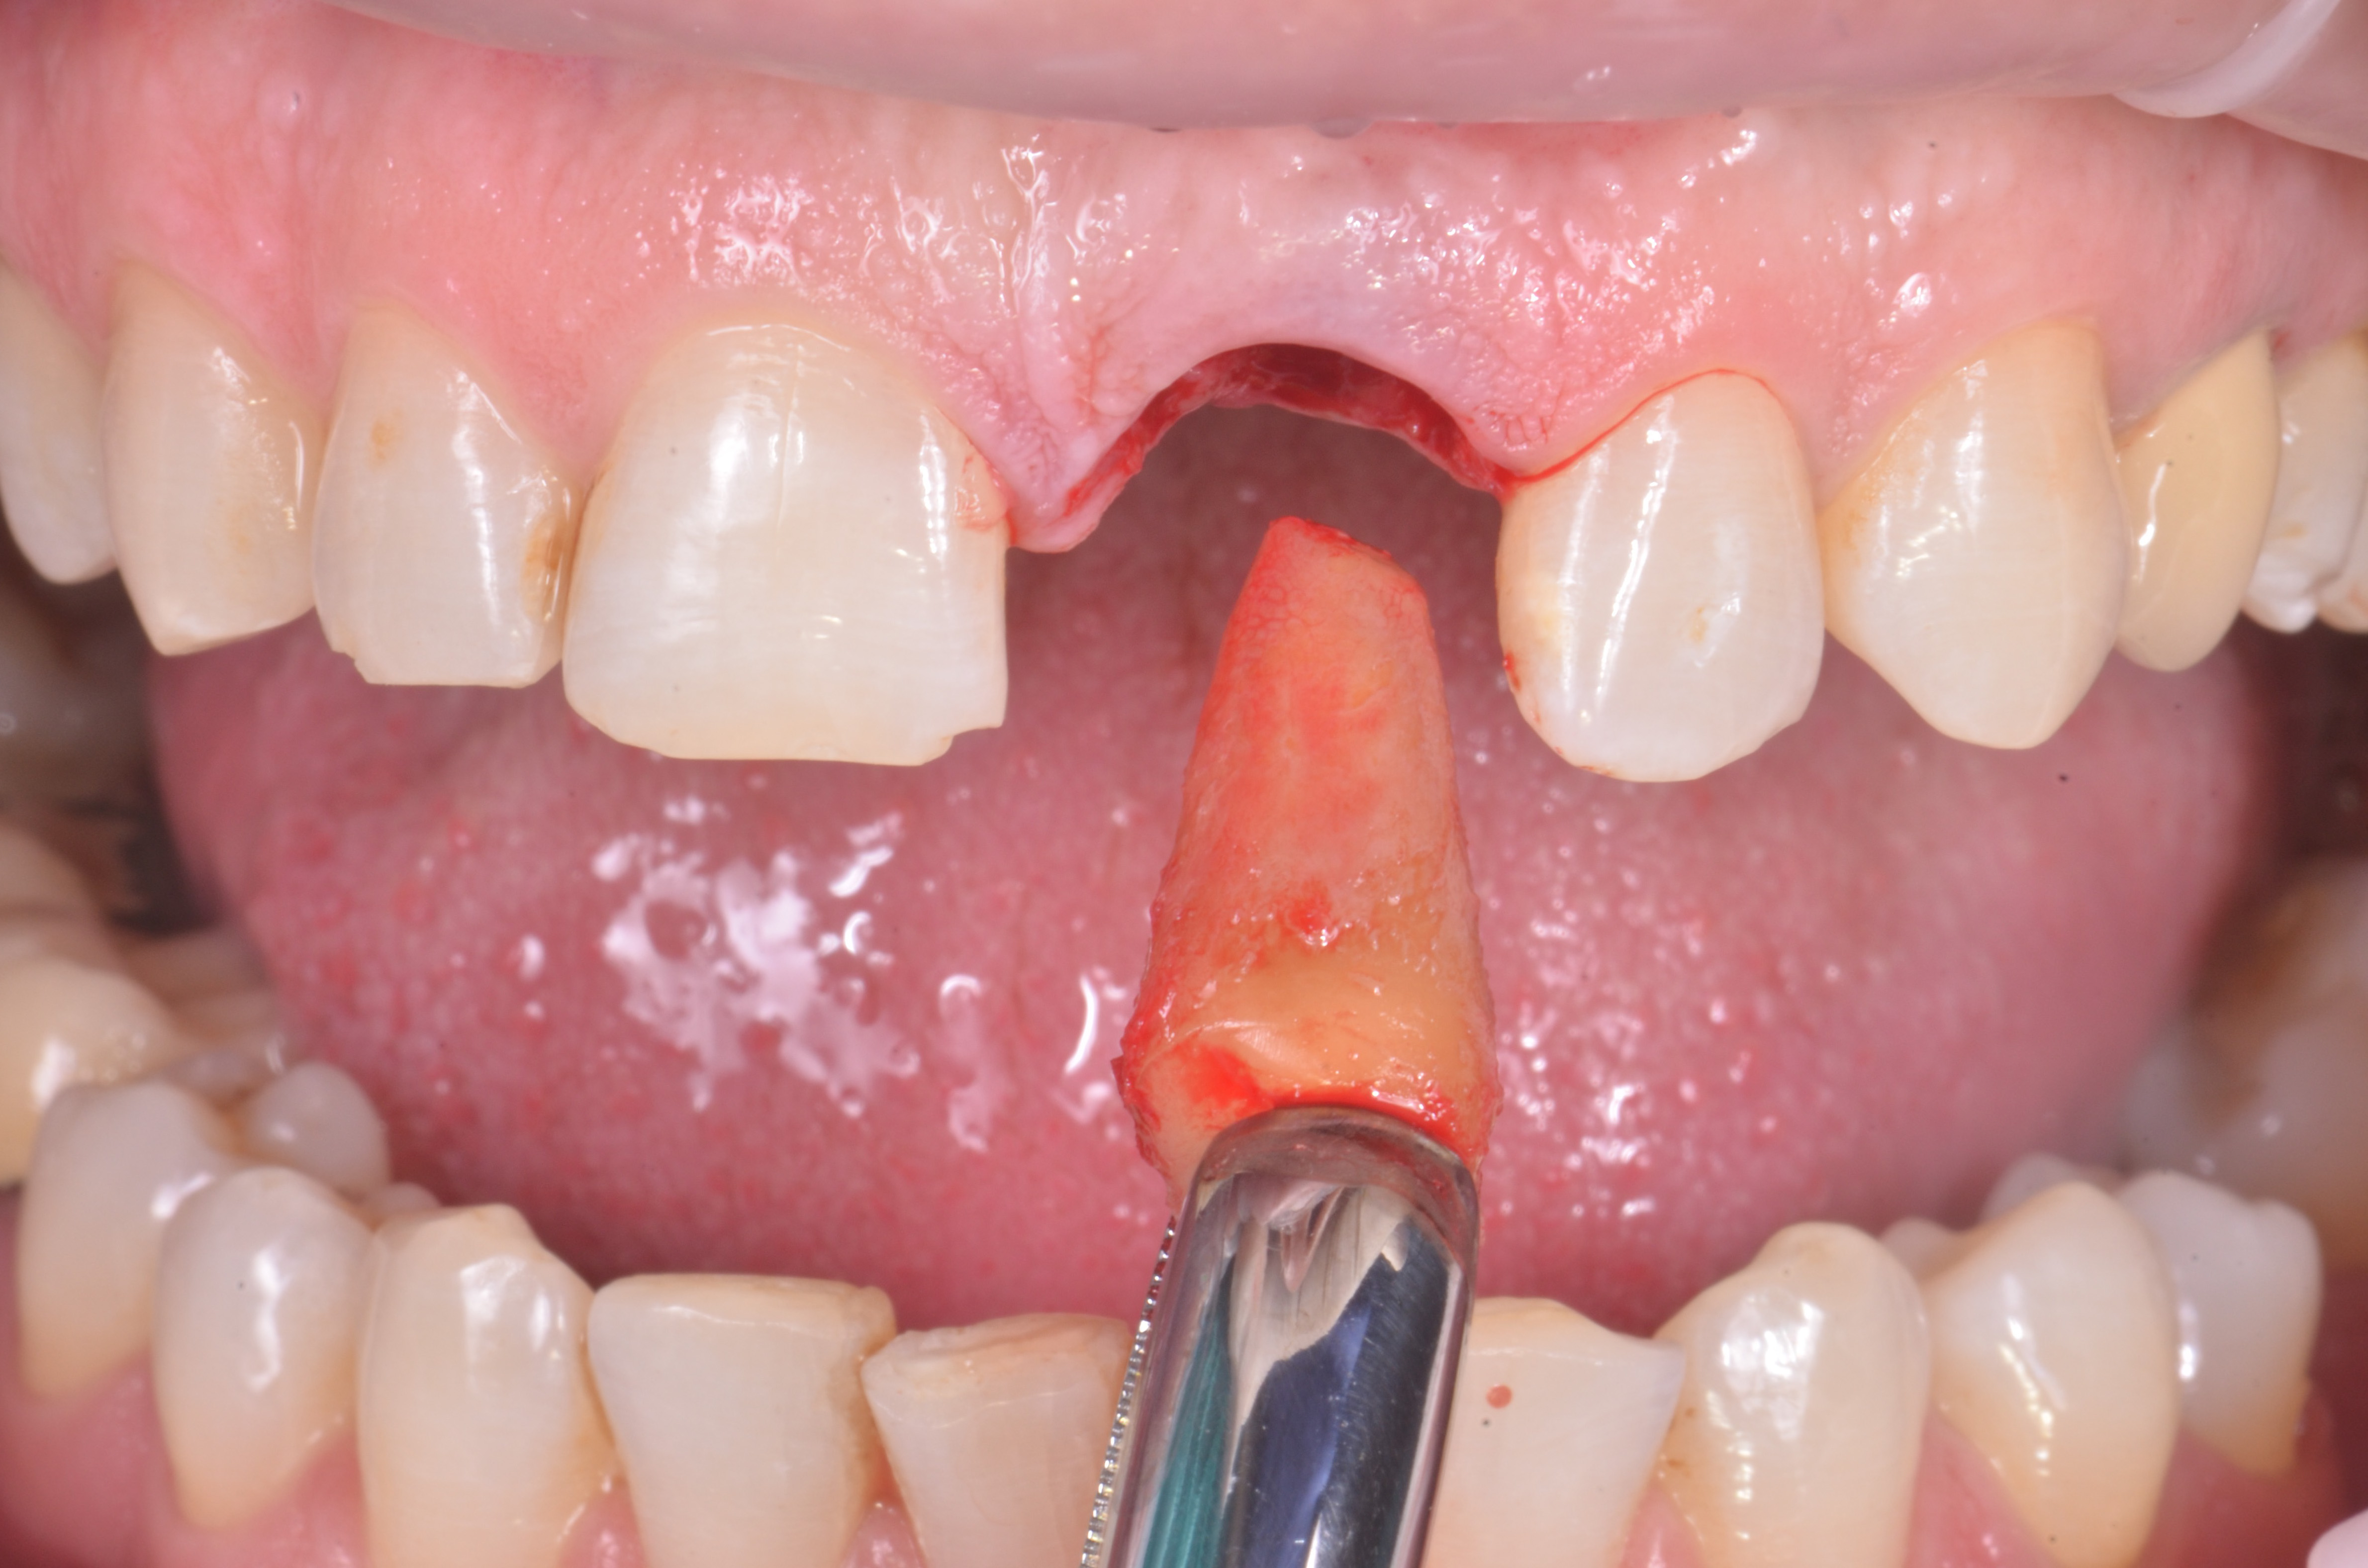

Previa somministrazione di anestesia plessica, l’elemento 2.1 è stato estratto con una procedura minimamente invasiva senza sollevare lembi (fig.6).